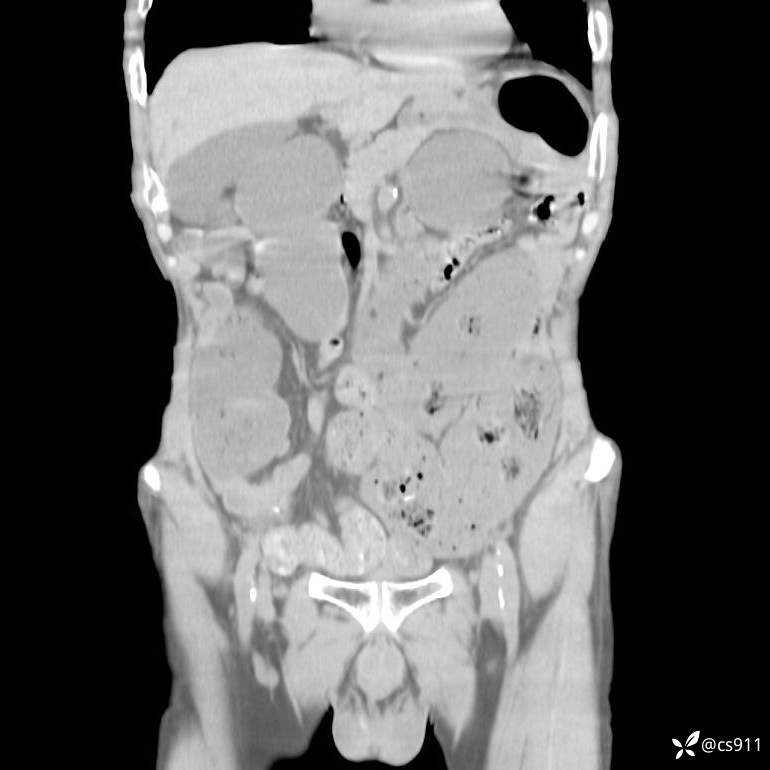

急腹症之急诊CT,原因?答案公布

男,77岁,腹痛、腹胀伴恶心呕吐1天。呕吐胃内容物,非喷射性呕吐,有咖啡色样胃内容物,诉有胃穿孔病史。查体:全腹平,下腹部压痛,全腹无反跳痛,叩诊呈浊音,移动性浊音阴性,肠鸣音减弱,1-2次/分。肛检:直肠未扪及明显肿物,可触及大量粪块。

T 36.6℃ P 80次/分 R 26次/分 BP 100/60mmHg

白细胞(WBC) H 14.55 10e9/L 4-10

中性粒细胞百分率(NEUT%) H 85.7 % 40-75

血淀粉酶(AMY) HH 1859 U/L 35-135

癌胚抗原(CEA) H 27.44 ng/ml 0-5

呕吐物 潜血试验 * 阳性 阴性

患者轮椅入室检查神志清楚, 能配合摆位和呼吸